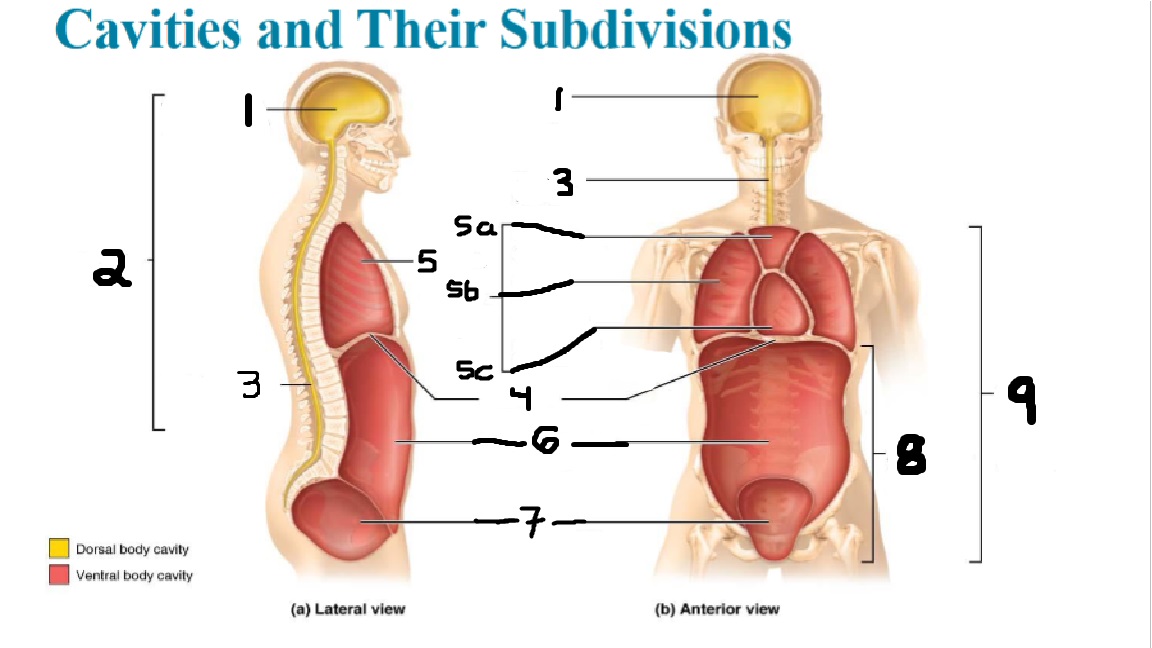

What cavities are part of the dorsal cavity?

The cranial and the Spinal (vertebral) cavities

What kind of cavity is labeled 2?

The dorsal body cavity (containing the cranial and spinal cavities)

What is the purpose of the dorsal cavity?

protects the nervous system

What is the main organ encased by the cranial cavity?

the brain

What cavity is labeled #1?

The cranial cavity

What is the main organ encased by the vertebral cavity?

the spinal cord

What is another word for the vertebral cavity?

the spinal cavity, or the spinal canal

What body cavity is labeled 3?

the vertebral cavity.

What cavities are included in the ventral cavity?

the thoracic, abdominal, and pelvic cavities.

What body cavity is labeled #6?

the abdominal cavity.

What are the main organs of the abdominal cavity?

the digestive organs such as the stomach, intestines, spleen and liver

What cavities are included in the Abdominopelvic cavity?

the abdominal cavity and the pelvic cavity

What body cavity is labeled #8?

The Abdominopelvic cavity

What does the diaphragm separate?

the thoracic and the abdominal cavities

What is labeled #4?

the diaphragm

What organs does the pelvic body cavity contain?

urinary/reproductive organs and rectum

What is labeled #7?

the pelvic cavity

What does the thoracic cavity encase?

the heart and the lungs

What is labeled #5?

the thoracic cavity

What part of the thoracic body cavity is labeled 5a?

superior mediastinum

What part of the thoracic body cavity is labeled 5b?

pleural cavity

What part of the thoracic body cavity is labeled 5c?

pericardial cavity within the mediastinum

What body cavity encloses the heart?

the pericardial cavity.